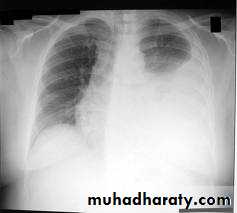

&Larger effusions: dullness to percussion, diminished breath sounds, and reduced tactile and vocal fremitus over the involved hemithorax.

&Large effusions (> 1500 mL), with concomitant atelectasis: bronchial breath sounds, egophony,

- (CXR) :The classical appearance of pleural fluid on the erect PA chest film is of a curved shadow at the lung base, blunting the costophrenic angle and ascending towards the axilla

Fluid appears to track up the lateral chest wall.

Around 200 mL of fluid is required to be detectable on a PA chest X-ray, but smaller effusions can be identified by ultrasound or CT.